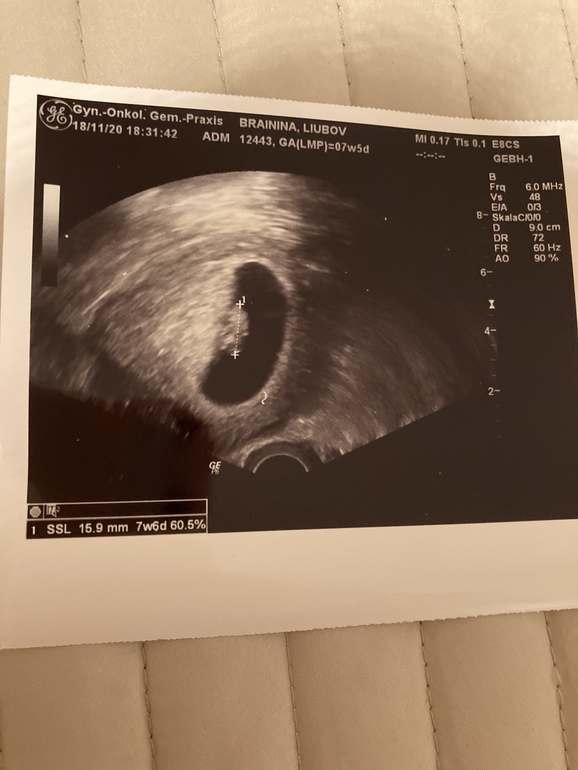

В ноябре я встала на учёт, долго думая нужно ли мне сразу сменить гинеколога, т.к. мой доктор онколог и я была не уверенна в его опыте ведения беременности. Всё таки стала на учёт у своего доктора, сдала все нужные анализы, он сделал мне 2 узи.

Во втором месте нужно было заранее сдать кровь на скрининг и после узи можно было сразу получить на руки рассчитанные риски. Малыш весь скрининг прятался куда-то вглубь, доктор сильно давил на живот датчиком и ещё и рукой с другой стороны, что бы подогнать ребёнка туда, куда нужно.😱 По скринингу все риски были очень низкие и доктор дал мне 93% гарантии, что малыш без патологий. Срок поставил почти на неделю больше, чем по м. Но я всё же настояла на нипте. Во время скрининга доктор показал мне срез между ножек малыша многозначительно кивнул. 😂 Пол он не имеет права говорить до 14 недель, но было видно, что это мальчик.😍